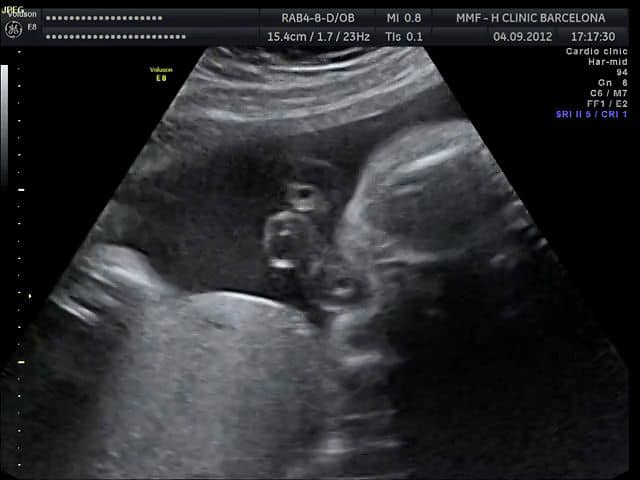

Semana a semana tu bebé fue tomando forma todos sus órganos se fueron desarrollando hasta tener la forma similar a la que tendrá a la hora de nacer. No hay aire dentro del saco amniótico. Alcanza fácilmente los 43 centímetros y pesa alrededor de 2 kilogramos.

Durante la semana 33 de embarazo el bebé sigue aumentando de peso y creciendo en longitud. En este momento el bebé puede ver el mundo líquido a su alrededor experimentar sensaciones cuando sujeta un dedo del pie o succiona un dedo prueba el líquido amniótico y escucha los latidos de tu corazón.

Lee sobre los cuidados del bebé y del posparto y conoce cómo cambia tu cuerpo en esta semana. En la semana 33 de gestación momento en que el bebé lleva 31 semanas formándose mide unos 43-45 cm y pesa cerca de 2000 gramos. Valoración de la anemia con una analítica. En la semana 33 de embarazo ya estás últimas semanas antes del parto los miles de millones de neuronas del cerebro del bebé lo están ayudando a aprender sobre el ambiente dentro del útero. Bebé listo para engordar. A estas alturas ya habrán comenzado las prisas con los preparativos para la llegada del pequeño y es probable. Encuentra toda la información sobre la semana 33 de embarazo.